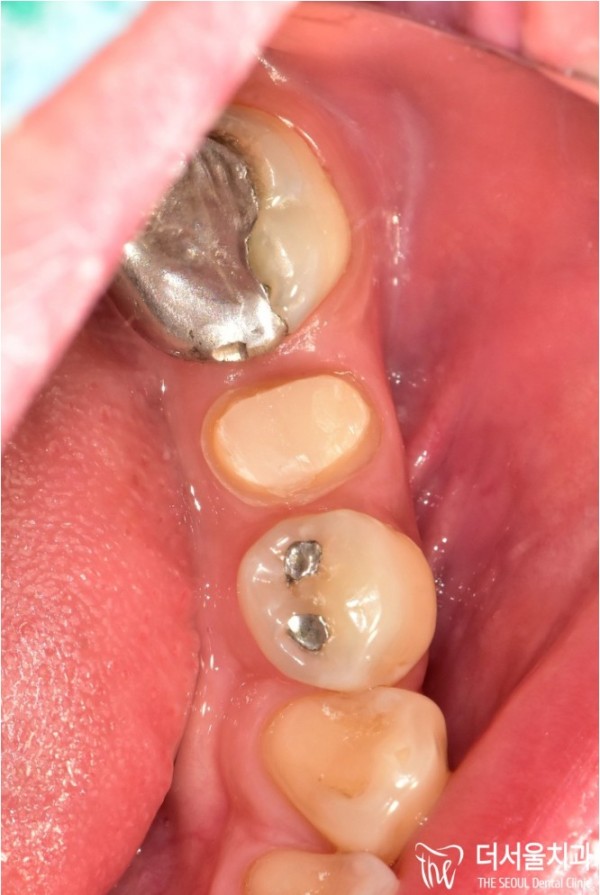

코어작업을 마친 치아에 크라운을 씌우기 위해

표면을 깔끔하고 예쁘게 다듬는 '프랩' 과정까지 마친 상태입니다.

To crown a tooth that's finished with core work

We've even finished the 'frap' process of trimming the surface neatly and prettily.